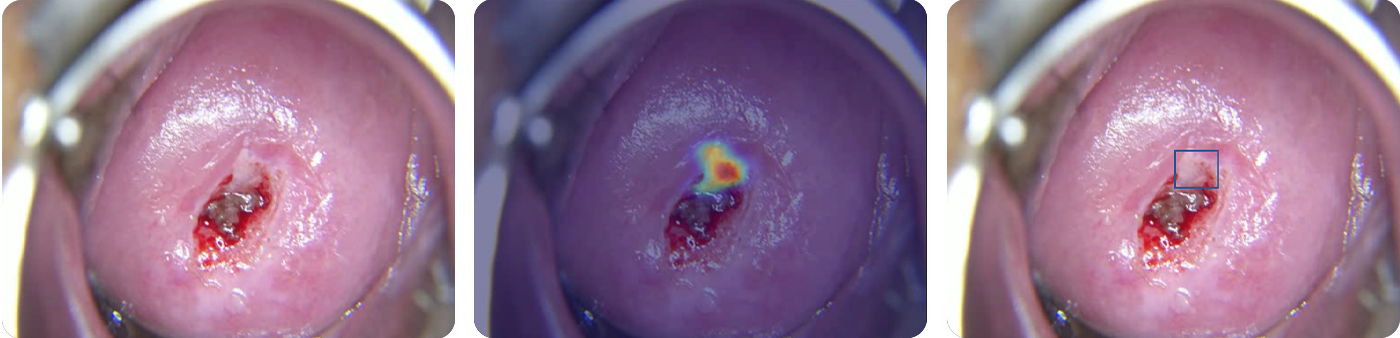

Cerviray AI

Normal

CIN1

CIN2-3

CIN3+